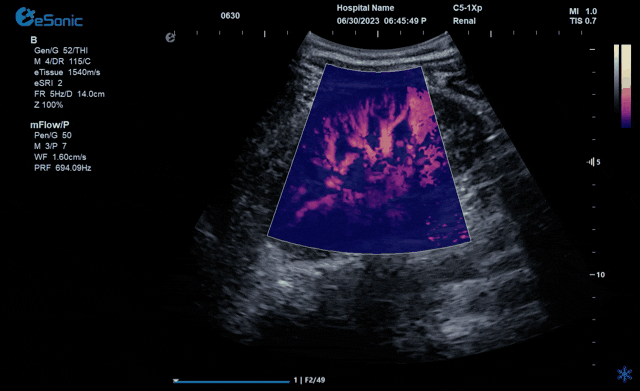

从影像学原理来看,低速血流检测的主要困难在于受血管周围的运动的影响。为了消除组织运动中的伪影,彩色多普勒血流显像采用壁滤波器。然而,此时微血管和低速血流与病变的临床信息也会被过滤。因此,CDFI只能显示直径最低大约0.2mm的血管和相对高速的血流。为突破这一困境,mFlow? 超微血流显像技术采用了一种更智能和独特先进的算法,能够有效地区分组织运动和血流运动产生的多普勒信号。mFlow? 应用更高的信噪比显示极低速血管和血流,由此可以检测到直径大约0.1mm左右的血管和速度低于1cm/s的血流。mFlow?技术不仅仅局限于线阵探头,在其他应用的探头中也有搭载,同时具备多种显示模式和方向的显示。可对极低速的血流速度进行测量和定量血管指数。大家可以把mFlow?应用到更多的临床疾病中去,让这项技术给广大临床医生带来更多的帮助。

↓不同模式下肾脏微血流动态图↓